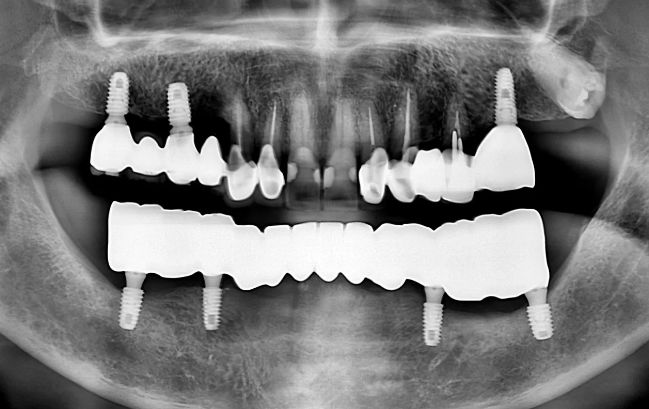

50대 남성, 원데이 수면 전체 임플란트 19개 식립